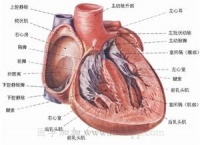

心肌(cardiac muscle) 由心肌细胞构成的一种肌肉组织。广义的心肌细胞包括组成窦房结、房内束、房室交界部、房室束(即希斯束)和浦肯野纤维等的特殊分化了的心肌细胞,以及一般的心房肌和心室肌工作细胞。前5种组成了心脏起搏传导系统,它们所含肌原纤维极少,或根本没有,因此均无收缩功能;但是,它们具有自律性和传导性,是心脏自律性活动的功能基础;后两种具收缩性,是心脏舒缩活动的功能基础。

心肌细胞具有传导兴奋的特性。正常心脏的节律起搏点是窦房结,它所产生的自动节律性兴奋,可依次通过心脏的起搏传导系统,而先后传到心房肌和心室肌的工作细胞,使心房和心室依次产生节律性的收缩活动。心肌的兴奋在窦房结内传导的速度较慢,约0.05米/秒;房内束的传导速度较快,为1.0~1.2米/秒;房室交界部的结区的传导速度最慢,仅有0.02~0.05米/秒;房室束及其左右分枝的浦肯野纤维的传导速度最快,分别为1.2~2.0及2.0~4.0米/秒。

1.正常情况下,窦房结的自律性最高,它自动产生的兴奋依次激动心房肌、房室交界、房室束及其分支和心室肌,引起整个心脏兴奋和收缩。由于窦房结是正常心脏兴奋的发源地,又是统一整个心脏兴奋和收缩节律的中心,故称为心脏的正常起搏点。故由窦房结控制的心跳节律,称为窦性节律。而正常情况下,窦房结以外的心脏自律组织因受窦房结兴奋的控制,不表现其自律性,故称为潜在起搏点。